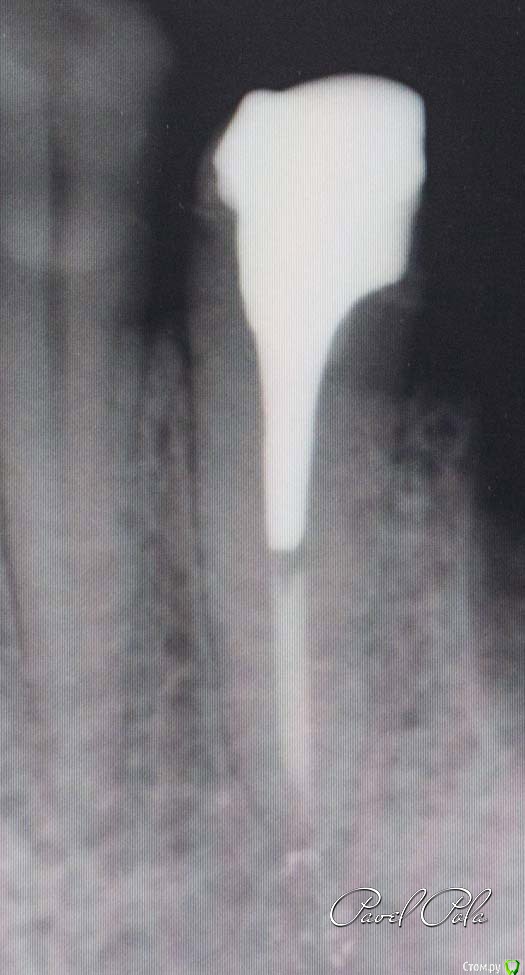

Л Ю С Я Опубликовано 27 декабря, 2016 Поделиться Опубликовано 27 декабря, 2016 Коллеги, совсем недавно была на эндодонтии номер 8 Соломонова. Там как раз было все про посты , про восстановление депульпированные зубов. Если для кого то его мнение авторитет: вкв по прежнему рулят! Ссылка на комментарий

Kolchanov Опубликовано 27 декабря, 2016 Автор Поделиться Опубликовано 27 декабря, 2016 Что-то он свое мнение поменял. Раньше говорил, что все это в архивах стоматологии. Делал исключение только для золота. Клял стекловолокно и не имел ничего против анкеров. Ссылка на комментарий

Л Ю С Я Опубликовано 28 декабря, 2016 Поделиться Опубликовано 28 декабря, 2016 Что-то он свое мнение поменял. Раньше говорил, что все это в архивах стоматологии. Делал исключение только для золота. Клял стекловолокно и не имел ничего против анкеров.Золото у него и сейчас в приоритете. Стекловолокно ничего не имеет против, но узкие показания, также как и анкера, но из стали. В основном вкв Ссылка на комментарий

Kolchanov Опубликовано 28 декабря, 2016 Автор Поделиться Опубликовано 28 декабря, 2016 Вот так вот. 8 лет прошло и все перевернулось. Может и амальгамой теперь можно билдапить, заводя ее в каналы, не говорил? Ссылка на комментарий

Л Ю С Я Опубликовано 28 декабря, 2016 Поделиться Опубликовано 28 декабря, 2016 Вот так вот. 8 лет прошло и все перевернулось. Может и амальгамой теперь можно билдапить, заводя ее в каналы, не говорил?Коронорадикулярное восстановление прямой путь к трещине Ссылка на комментарий